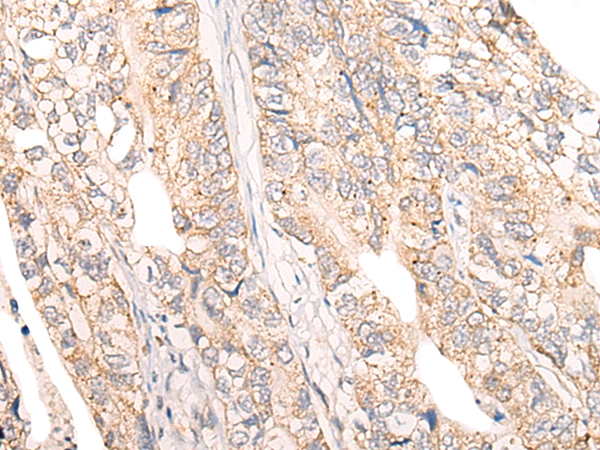

The image on the left is immunohistochemistry of paraffin-embedded Human thyroid cancer tissue using 46535(COPS8 Antibody) at dilution 1/20, on the right is treated with fusion protein. (Original magnification: x200)

The image on the left is immunohistochemistry of paraffin-embedded Human gastric cancer tissue using 46535(COPS8 Antibody) at dilution 1/20, on the right is treated with fusion protein. (Original magnification: x200)